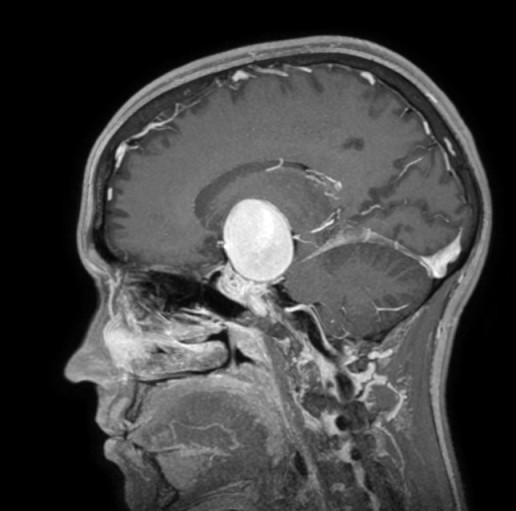

“L’aneurisma cerebrale è una patologia acquisita nella quale la parete di un’arteria cerebrale si sfianca e forma un palloncino che rischia di esplodere. In questo caso si trattava di un rigonfiamento dell’arteria carotide interna del diametro di ben 4 cm (gli aneurismi vengono definiti giganti sopra i 2,5 cm)” – spiega Marco Cenzato, Direttore della Neurochirurgia. “Spesso gli aneurismi rimangono silenti oppure vengono riscontrati in maniera accidentale durante esami diagnostici per altre problematiche. Quando si manifestano è perché stanno diventando instabili e il rischio di rottura è altissimo, con esito, purtroppo, spesso letale”.

L’intervento, eseguito dall’équipe della Neurochirurgia dell’Ospedale Niguarda, si è dimostrato, come previsto, molto complesso: ci sono volute sette ore per chiudere temporaneamente la carotide, escludere l’aneurisma e ricostruire il corretto flusso nei vasi cerebrali.